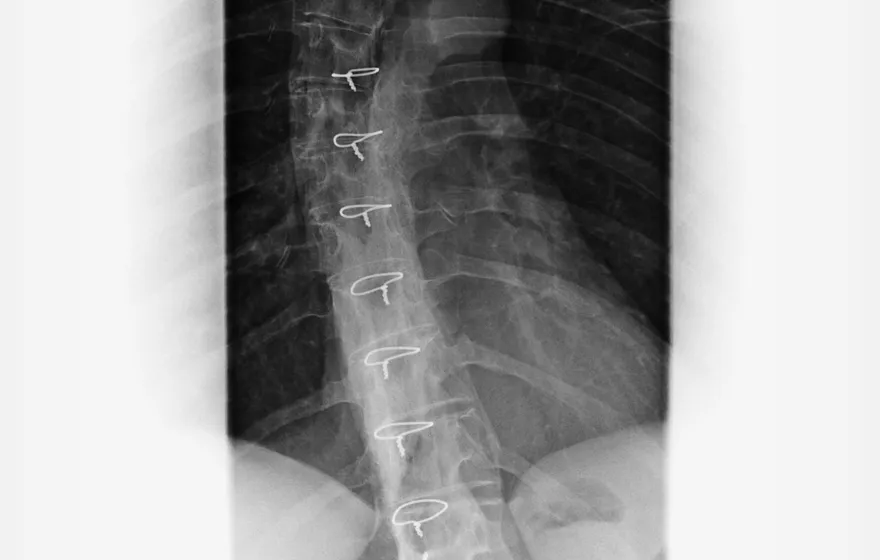

腰痛別只怪老化!醫搖頭:久坐才是椎間盤退化的真正元凶

椎間盤

椎間盤退化

久坐腰痛

核心穩定

腰椎健康